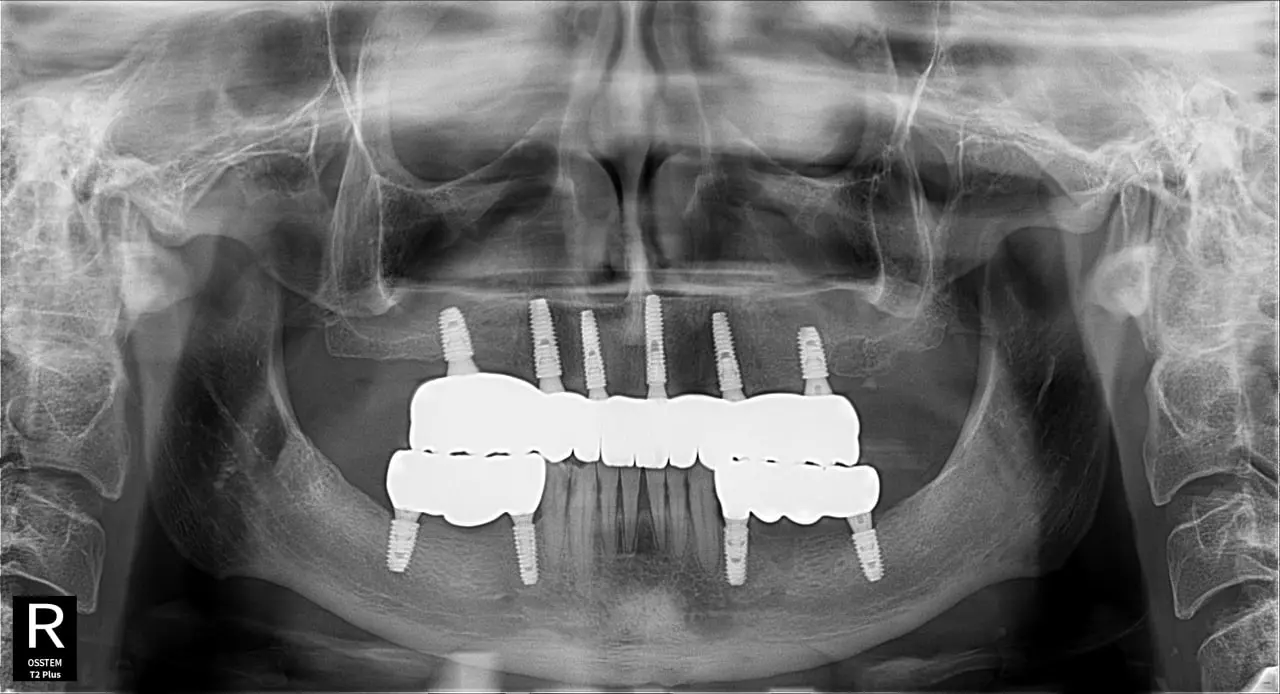

Наші роботи

Встановлення зубного імпланта у Млинові